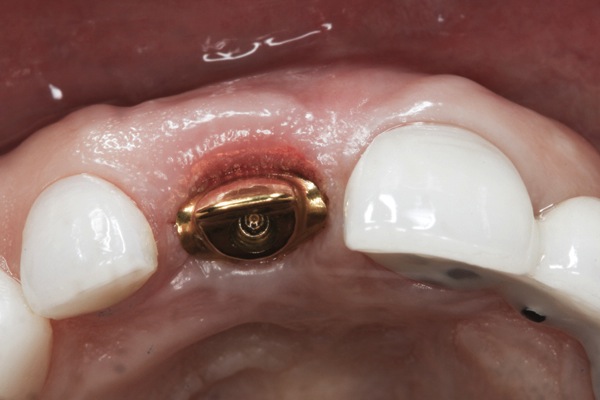

The master cast and abutment were returned to the laboratory for fabrication of the restoration (Figure 15). An all-ceramic crown (e.max®, Ivoclar Vivadent) was fabricated on the custom abutment; it matched the contours of the adjacent central incisor. After completion of custom shading, the definitive abutment and crown were returned to the restorative dentist. The abutment was tried in (Figure 16), and a radiograph was taken to confirm complete seating between the abutment/implant and the crown/abutment. The definitive abutment screw was torqued to 20 Ncm, and the screw-access opening was blocked out with Teflon tape.

Fig 16. Try-in of the definitive titanium-nitride–coated abutment.